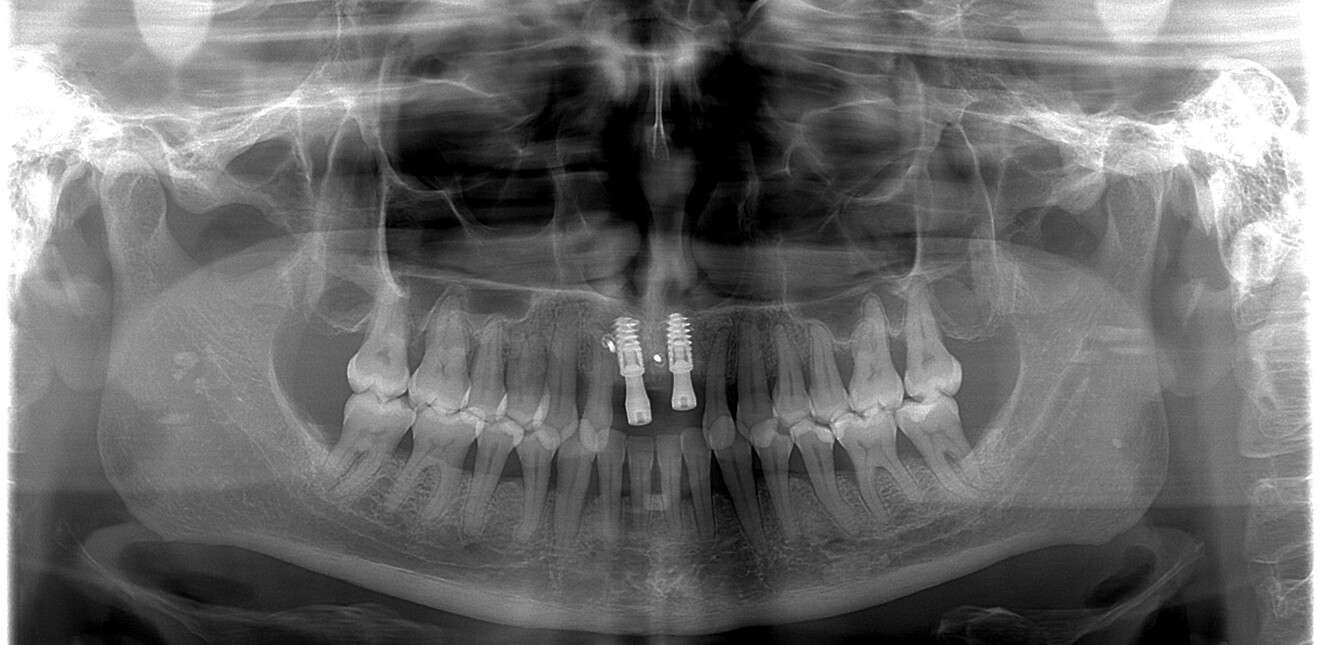

Nous réalisons un lambeau avec une incision crestale décalée en palatin en 11 et 21, sulculaire en 12, 13, 22, 23, en prenant soin de préserver les papilles interdentaires, ainsi que deux décharges verticales en distal des canines. Nous réalisons un décollement de pleine épaisseur (Figs. 28 et 29). Les dents (12, 22 et 18) sont facilement extraites et les alvéoles curetées avec soins. Deux implants (4*13) sont positionnés dans la paroi palatine des alvéoles, il subsiste une déhiscence vestibulaire en 22. Les racines de 12, 22 et 18 sont séparées dans le sens de la longueur. Les racines préparées comme indiqué ci-dessus, sont vissées en vestibulaire et en occlusal de la crête, au moyen de vis d’ostéosynthèse (diamètre 0,9 mm), afin de reconstruire la crête osseuse au niveau des inters de bridge ainsi que la paroi vestibulaire de la crête au niveau de 22 (Figs. 30 et 31). Le gap vestibulaire entre les implants et la crête ainsi que l’espace entre la crête et le greffon au niveau de 21, sont comblés avec un matériau d’origine synthétique (Collapat II Symatese). Le lambeau est tracté, suturé coronairement avec un fil tressé synthétique 5.0 (Fig. 32). Des piliers coniques droits pour prothèse plurale transvissée sont posés, et une empreinte prise à la fin de l’intervention (Fig. 33). Un provisoire est réalisé dans la journée par notre laboratoire de prothèse et posé le soir même. (Figs. 34 et 35)

Les sutures sont retirées à 15 jours. Un contrôle de la bonne ostéointégration des implants est réalisé à 2 mois postopératoire (Figs. 36 et 37). La réalisation de la prothèse d’usage par notre correspondant intervient à 9 mois postopératoire (Fig. 38).